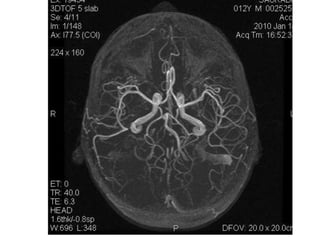

Arteries of the brain (cranial view) - MRA

1. Anterior cerebral artery

2. Anterior communicating artery

3. Basilar artery

4. branches (in insula) of middle

cerebral artery

5. Cavernous portion of internal carotid

artery

6. Cervical portion of internal carotid

7. Genu of middle cerebral artery

8. Intracranial (supraclinoid) internal

carotid artery

9. Middle cerebral artery

10. Ophthalmic artery

11. Petrous portion of internal carotid

12. Posterior cerebral artery

13. Posterior cerebral artery in ambient

cistern

14. posterior cerebral artery in

interpeduncular cistern

15. Posterior communicating artery

16. Posterior inf cerebellar artery.

17. Quadrigeminal portion of posterior

18. Superior cerebellar artery

19. Vertebral artery